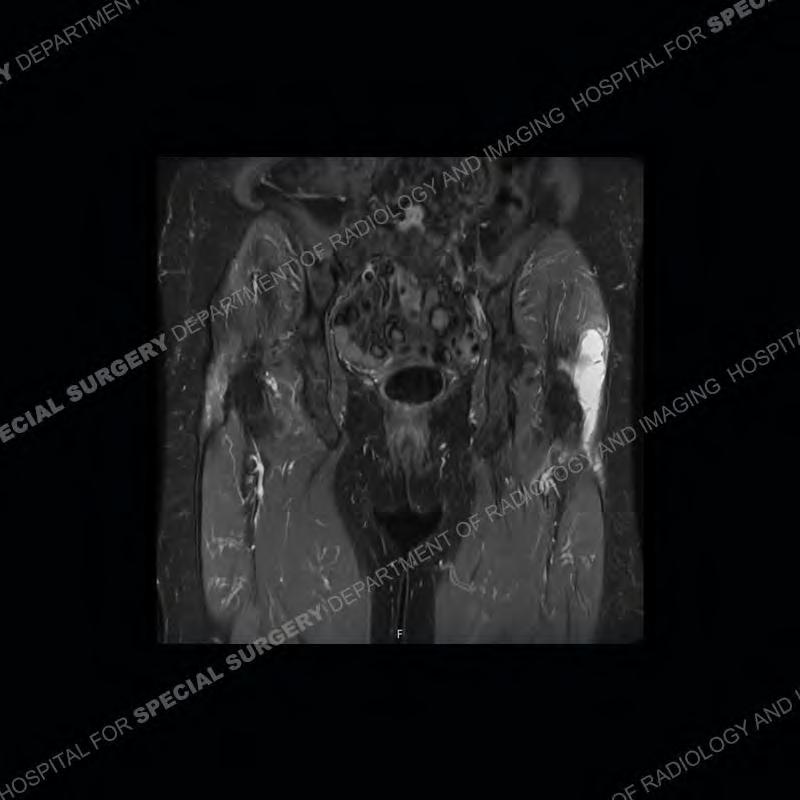

The radiograph is not particularly contributory in this case. The MRI demonstrates markedly abnormal architecture of the gluteus minimus and anterolateral band of the gluteus medius. Portions of the tendons are high signal, portions are highly attenuated, and portions are disrupted. A large, complex fluid collection is present in the adjacent soft tissue.

Diagnosis: Gluteal Tendinosis and Disruption with Complex Trochanteric Bursal Collection

Not as much of a diagnostic dilemma as many of the other cases shown but just a nice example of the pathology seen of the gluteal tendons and a cause of trochanteric pain. Although, frequently thought of in isolation, trochanteric bursitis or bursal thickening is much more commonly a reactive change to underlying pathology of the subjacent gluteal tendons. The gluteus medius is divided into a posterior band and an anterolateral band. Tendinosis and partial tearing very commonly will involve the gluteus minimus and especially the more posterior fibers and then propagate into the anterior lateral band of the gluteus medius. Involvement of the posterior band of the medius is much less common and engenders a marked degree of functional impairment.

The bursae about the greater trochanter can be a little bit confusing especially given the terminology. Trochanteric bursitis is implied to mean the subgluteus maximus bursa which is present deep to the maximus and just lateral/superficial to the trochanter. That is the bursa involved in this case. In this case the complexity of the bursa relates to the tendon tearing with inflammatory change and probably hemorrhage accounting for the complexity. Two other, less frequently involved bursa are also present. The subgluteus medius and subgluteus minimus bursa are found just deep to the named tendons. Although pathology does frequently follow the previously described pattern it is possible to have isolated pathology to either the medius or minimus.